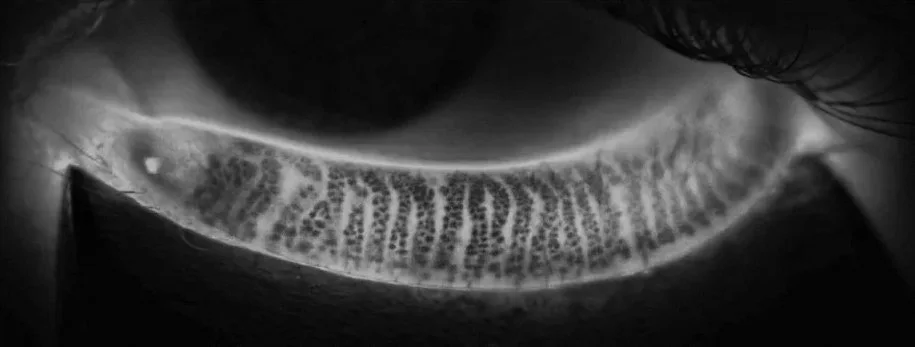

La meibographie est une image représentant l’état des glandes de Meibomius et permettant de détecter des atrophies. Il s’agit d’un test par transillumination grâce auquel nous pouvons identifier une perte partielle ou totale des structures visibles des glandes de Meibomius. La destruction des glandes de Meibomius est la marque de dysfonctionnements meibomiens, mais la meibographie peut aussi être utile pour diagnostiquer d’autres maladies touchant la surface oculaire.

MODIFICATIONS STRUCTURALES DES GLANDES DE MEIBOMIUS